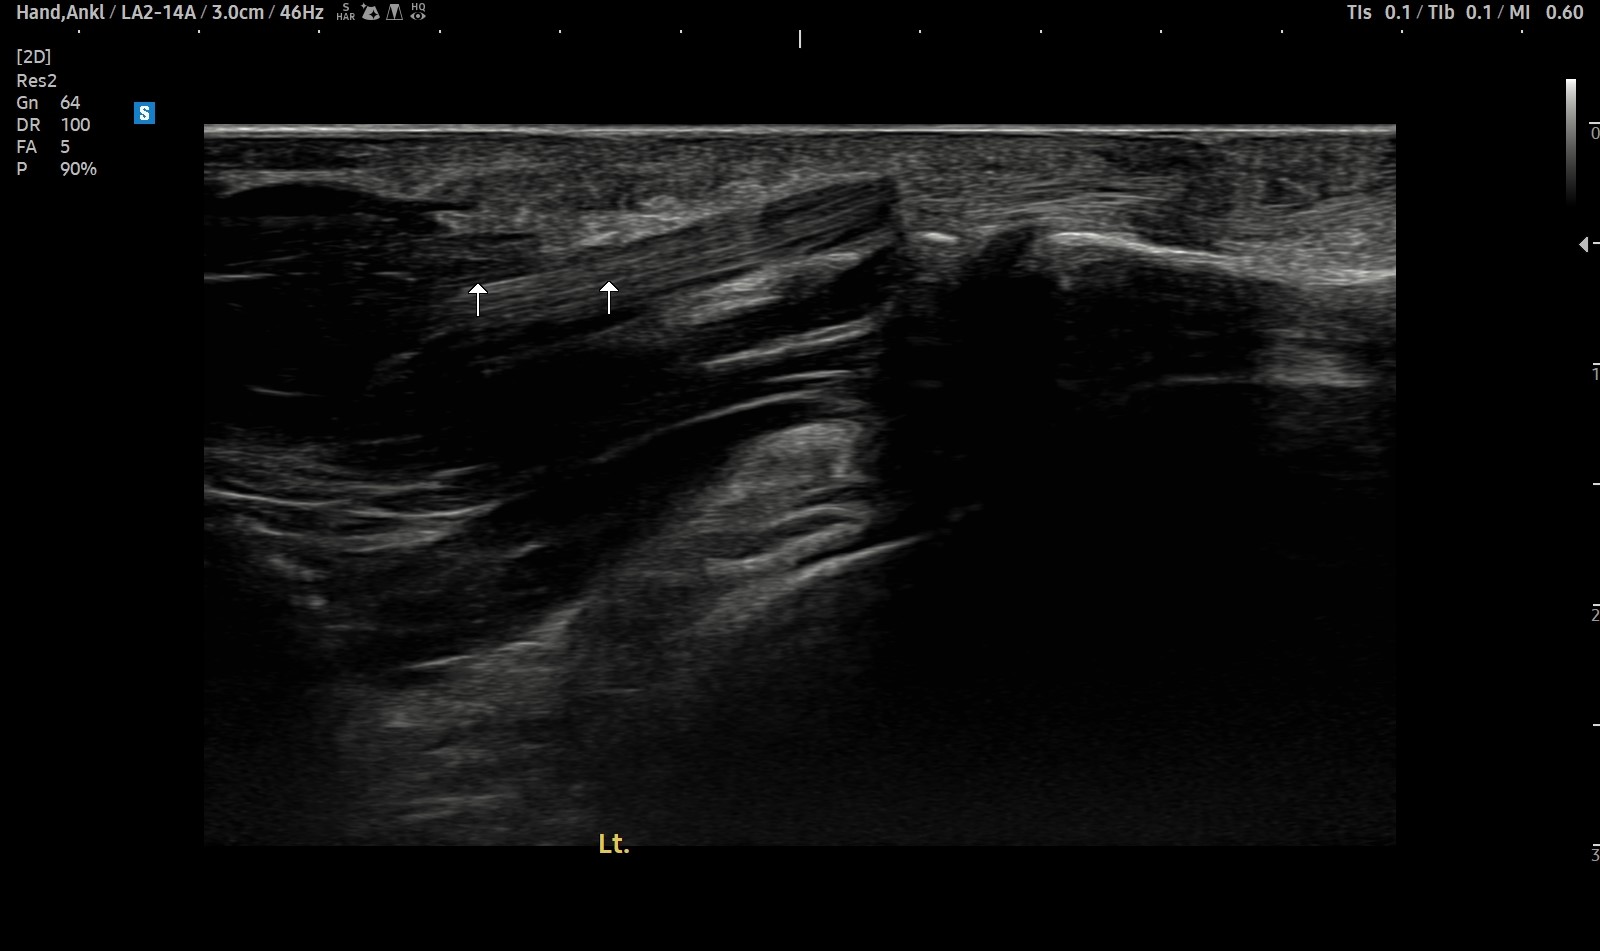

- 치료기간 : 25 . 5 . 7 ~ 25 . 8 .12

- 치료횟수 : 4cycle(20) 회

치료전

치료후